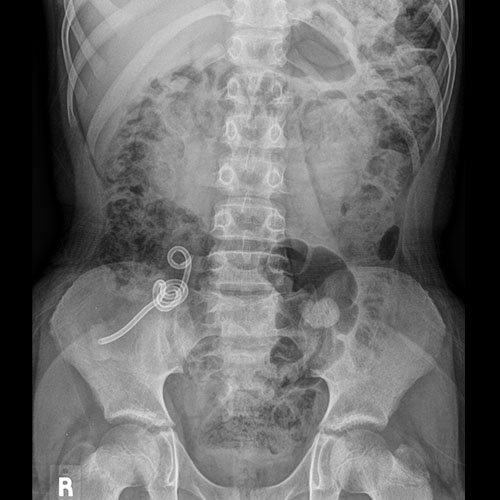

There is an unexpected radiopaque foreign body or incidental non-surgical foreign body in the abdomen or pelvis. [Yes/No]

Procedural

An -----French straight catheter was inserted just into the rectum. [Yes/No]

Under fluoroscopic guidance, the rectum and colon were filled with contrast, and fluoroscopic images were obtained. [Yes/No]

The colon was filled through its entire length, confirmed by contrast filling of the appendix and reflux into terminal ileum. [Yes/No]

The colon was partially filled. [Yes/No]

There are filling defects. [Yes/No]